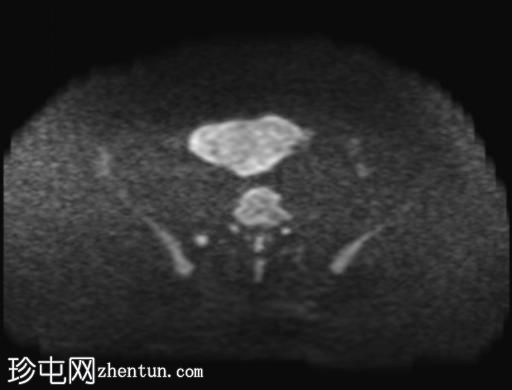

轴位

T2加权像

盆腔内可见多个边界清晰的肿块:

其中一个位于子宫上方,T2加权像呈中等信号,中心区域呈高信号,增强T1脂肪抑制像未见强化。右侧卵巢增大,增厚的血管蒂扭曲,未见强化,轴位和矢状位T2加权像均显示清晰。

另一个位于子宫后窝,T2加权像呈中等信号,增强扫描显示明显强化。

轻度腹腔积液